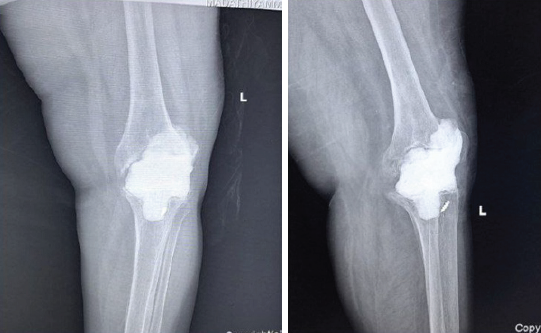

The patient underwent removal of all prosthetic components with radical debridement of infected and necrotic tissue. During tibial component removal, an iatrogenic quadriceps tendon avulsion occurred and was repaired using non-metallic suture anchors, restoring extensor mechanism continuity [13,14,15,16]. Following tendon repair, a hand-moulded antibiotic-loaded cement spacer containing vancomycin and gentamicin was inserted [6] (Fig. 2). Postoperatively, culture-directed intravenous antibiotics were administered for 3 weeks, followed by 3 weeks of oral antibiotics, completing a total antibiotic duration of 6 weeks after Stage I.The duration and sequencing of intravenous followed by oral antibiotic therapy were guided by established antimicrobial treatment principles for implant-associated infections. [13]

Figure 2: Post-operative anteroposterior and lateral radiographs following placement of an antibiotic-impregnated cement spacer after complete implant removal.